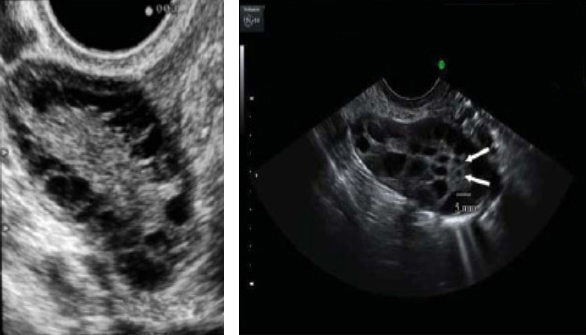

3) 초음파상 다낭성 난소